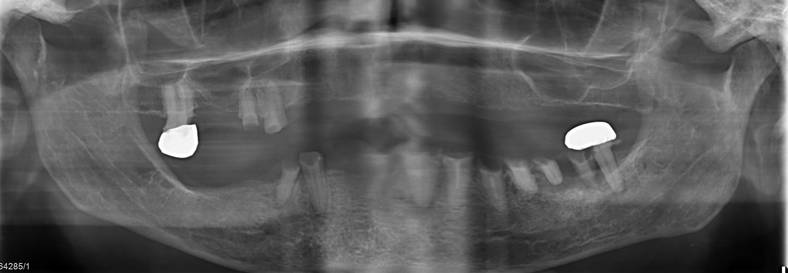

Operative Zahnentfernung / Chirurgische Zahnsanierung

Die Extraktion von Zähnen und Zahnwurzelresten bei gerinnungsgestörten, multimorbiden, neurologisch erkrankten oder geistig retardierten Patienten kann sich oft als komplex erweisen und erfordern nicht selten die zusätzliche stationäre Überwachung.

Chirurgische Zahnsanierungen bei multimorbiden Patienten mit schweren Herz-Kreislauf- oder Atemwegserkrankungen können häufig ebenfalls nicht in der zahnärztlichen Praxis durchgeführt werden. Nicht selten ist eine postoperative Überwachung dieser Patienten auf einer unserer Intensiv- oder Überwachungsstationen notwendig.